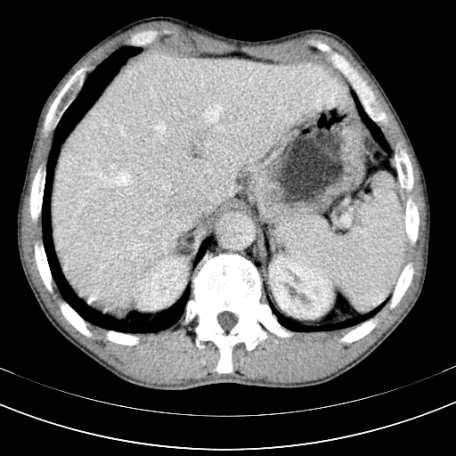

标题: CT21441:男55岁,上腹部胀痛半年余,请老师们看看是后腹膜淋巴 [打印本页]

标题: CT21441:男55岁,上腹部胀痛半年余,请老师们看看是后腹膜淋巴

眼拙!仅见胰腺稍丰满,脾大。

腹主动脉右侧有一个,有肿瘤病史吗?

转移瘤或淋巴瘤

腹膜后淋巴结肿大,原因待查。